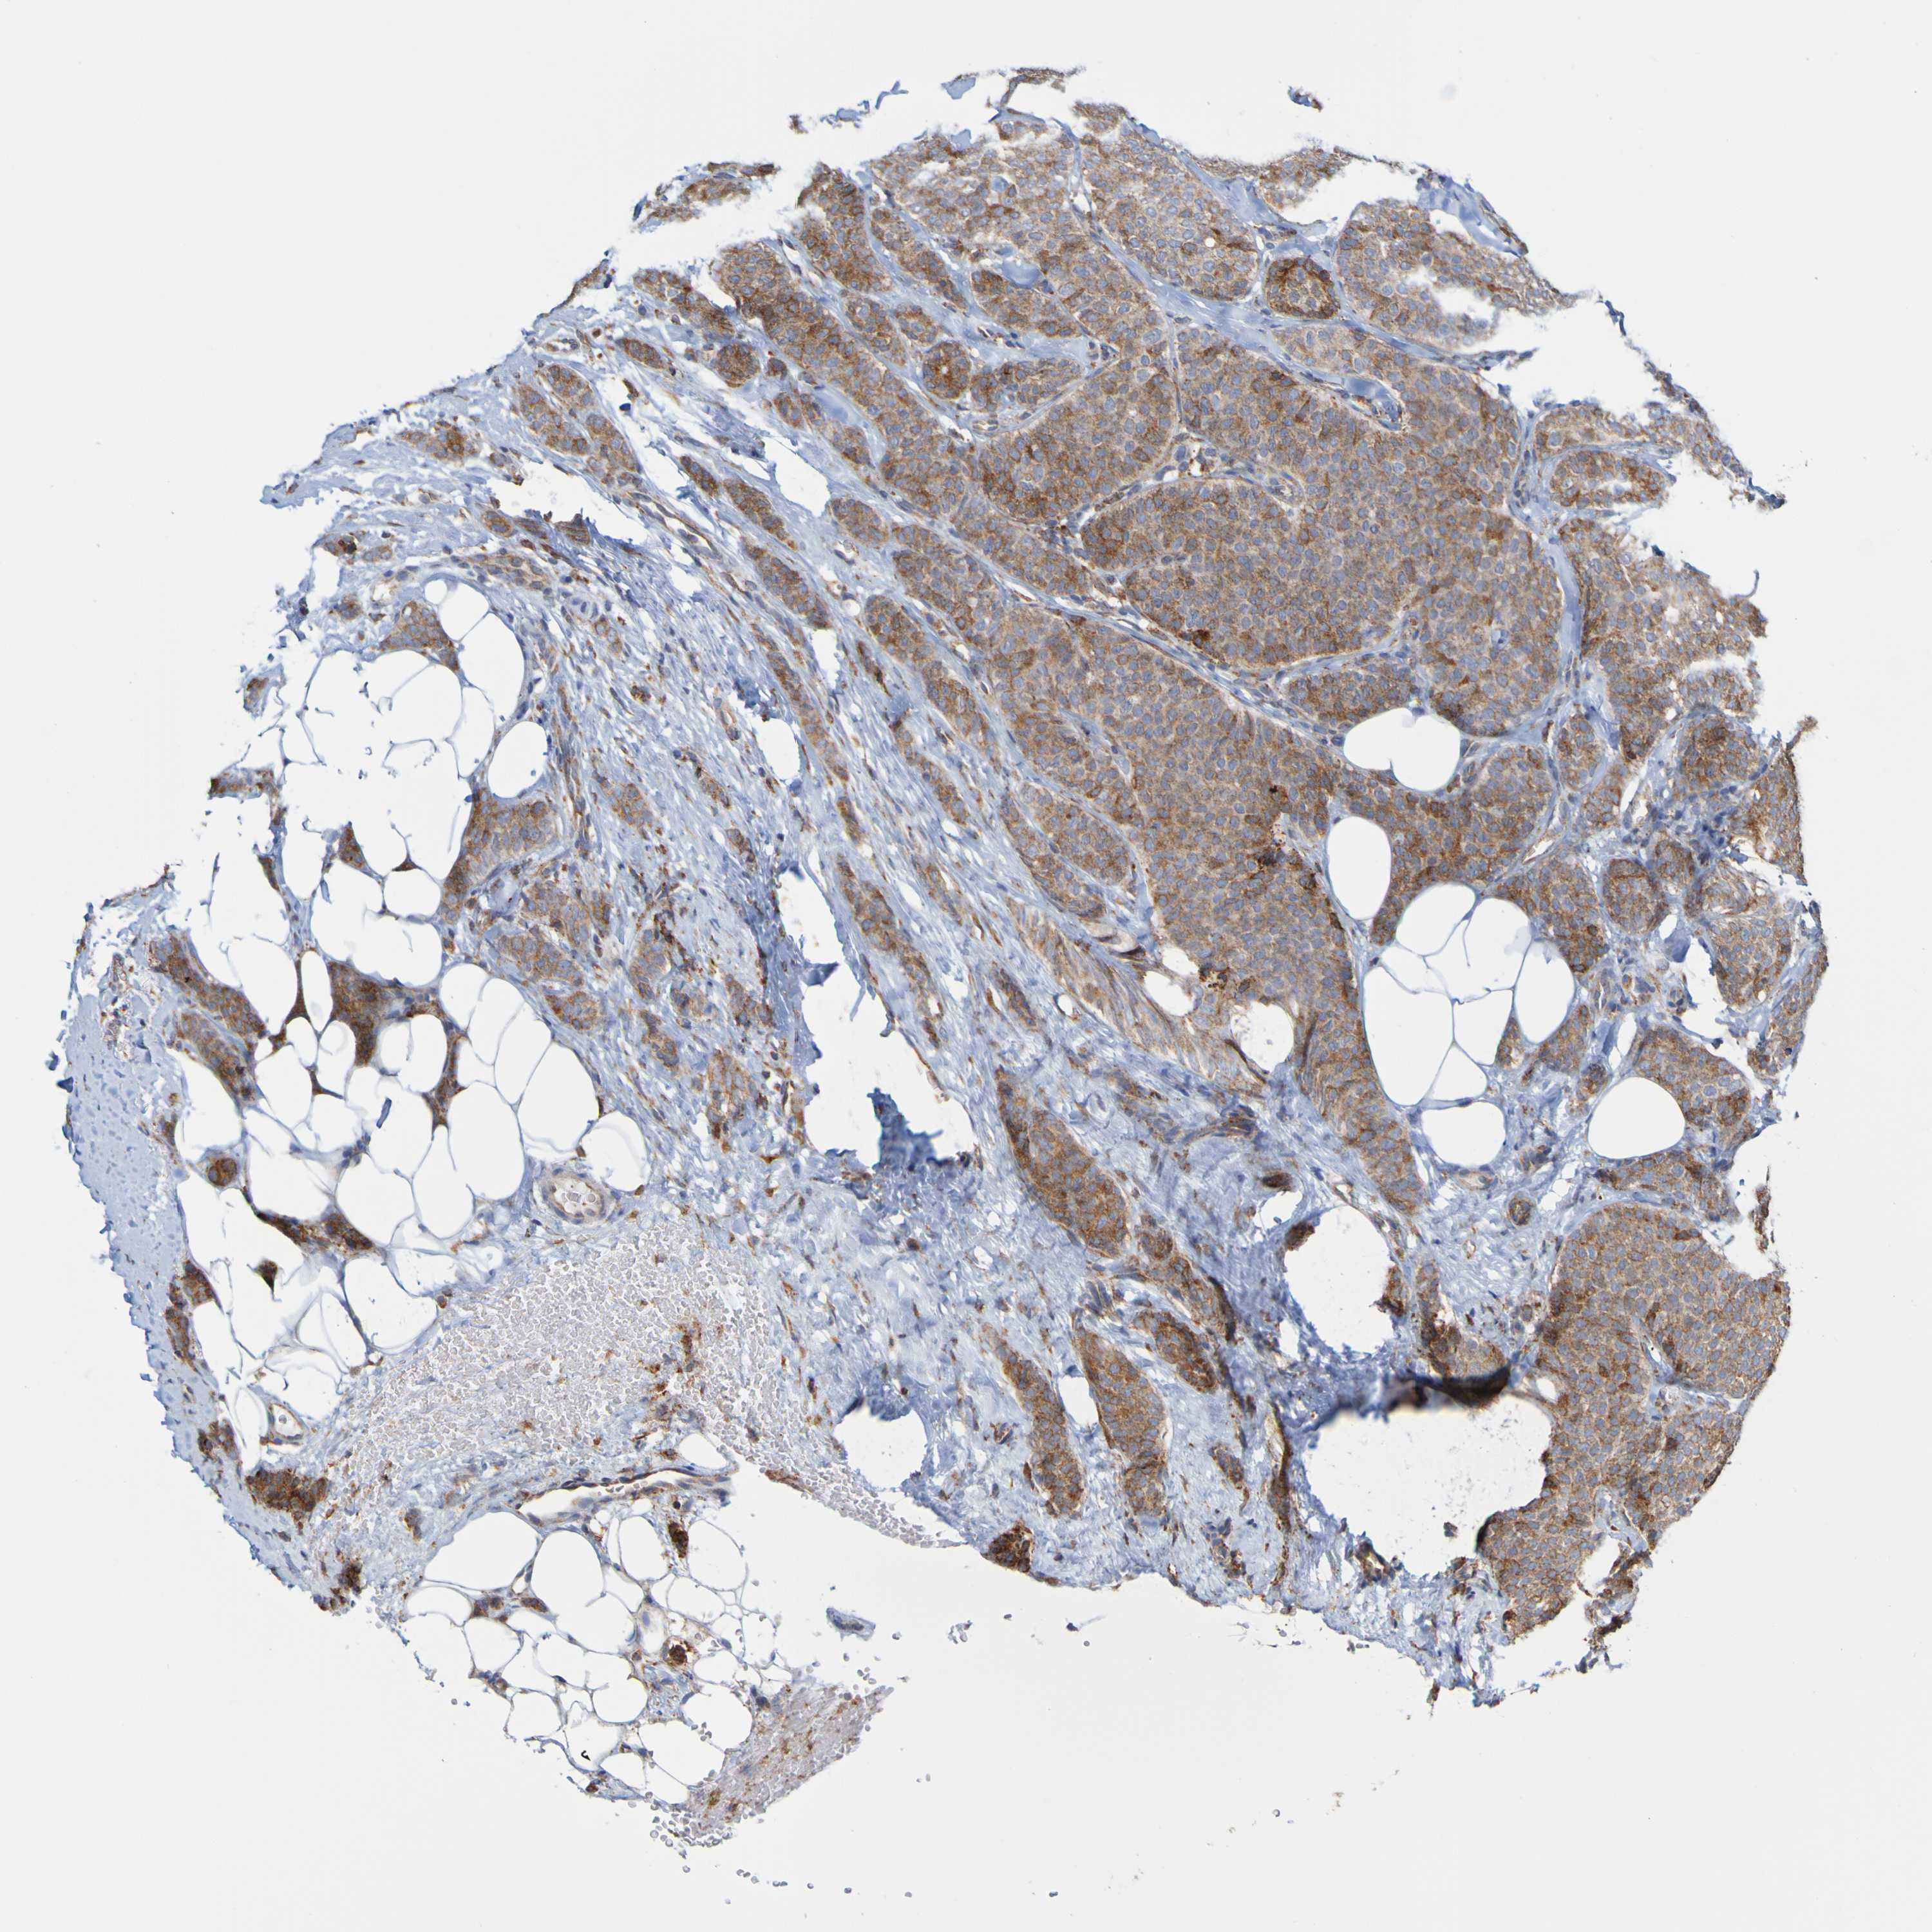

CANCER BREAST CANCER Show tissue menu

BRCA TCGA BRCA VALIDATION PROTEIN EXPRESSION